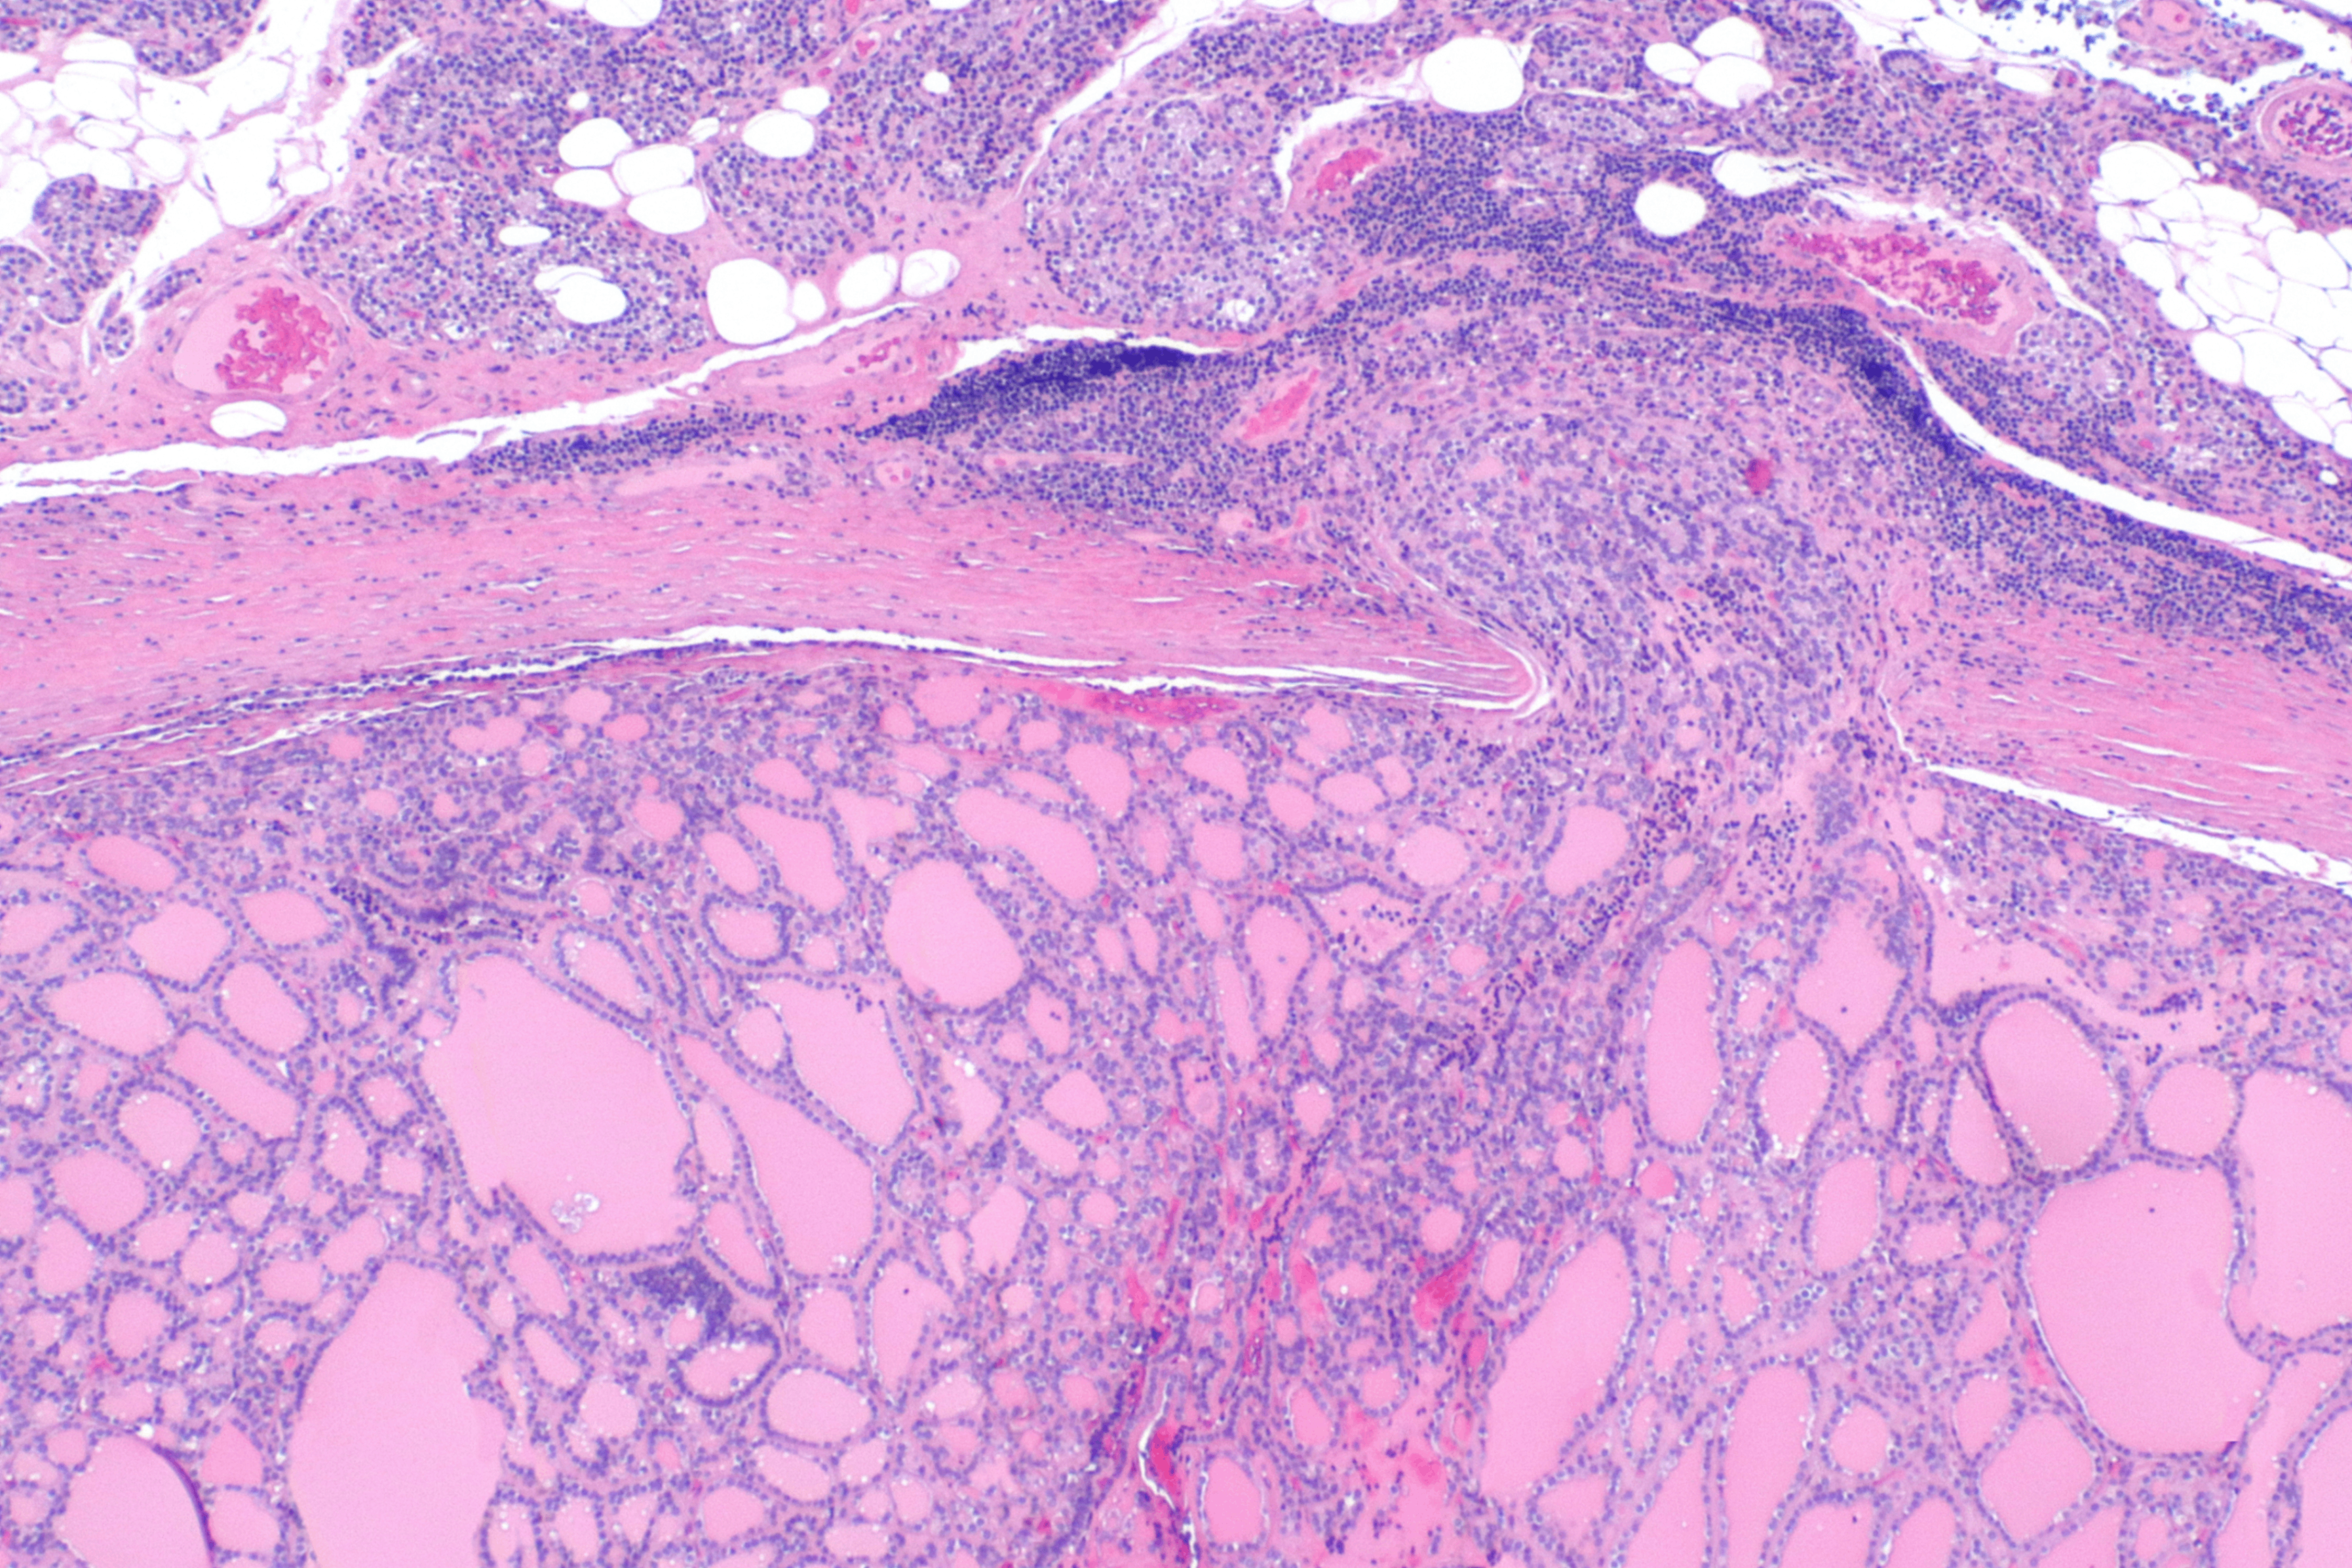

(2) 조직학적 소견

• 단일 결절

정상 갑상선 조직과 유사한 형태를 가짐

• 어떤 경우에는 여포 분화가 불분명하여 콜로이드 없이 세포 집합으로 존재

• 일부는 과립성, 호산성 세포질의 Hurthle cell로 구성됨

여포선종과 여포암의 감별은 세포학적으로 어려워 반드시 피막 및 혈관 침습 유무에 대한 조직학적 진단이 필요함

Follicular thyroid carcinoma, Wikipedia Commons